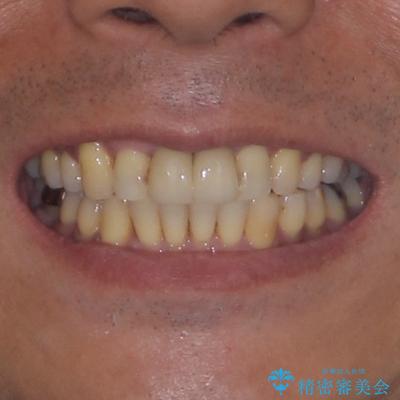

上顎前歯の突出感と右上の八重歯を気にされていたので、上顎左右の第一小臼歯2本を抜歯し、ワイヤー装置にて矯正治療を行うこととしました。

上顎前歯に装着されていた保険診療の前歯は見た目が気になるとのことであったので、矯正治療後にオールセラミッククラウンにて補綴治療を行うこととしました。

食いしばりにより奥歯がすり減っており、咬み合わせが定まるまで時間がかかりましたが、整った口もに仕上がりました。